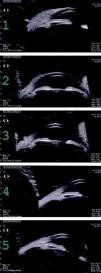

The patient was referred to the specialized center AC Camargo for a more thorough evaluation of the case. Digital retinography and ultrasound biomicroscopy demonstrated a homogeneous well-defined lesion close to the limbus, with medium reflectivity, extending over the cornea and with conjunctival thickening over the peripheral cornea, suggestive of fibrovascular proliferation (Figures 1 and 2).